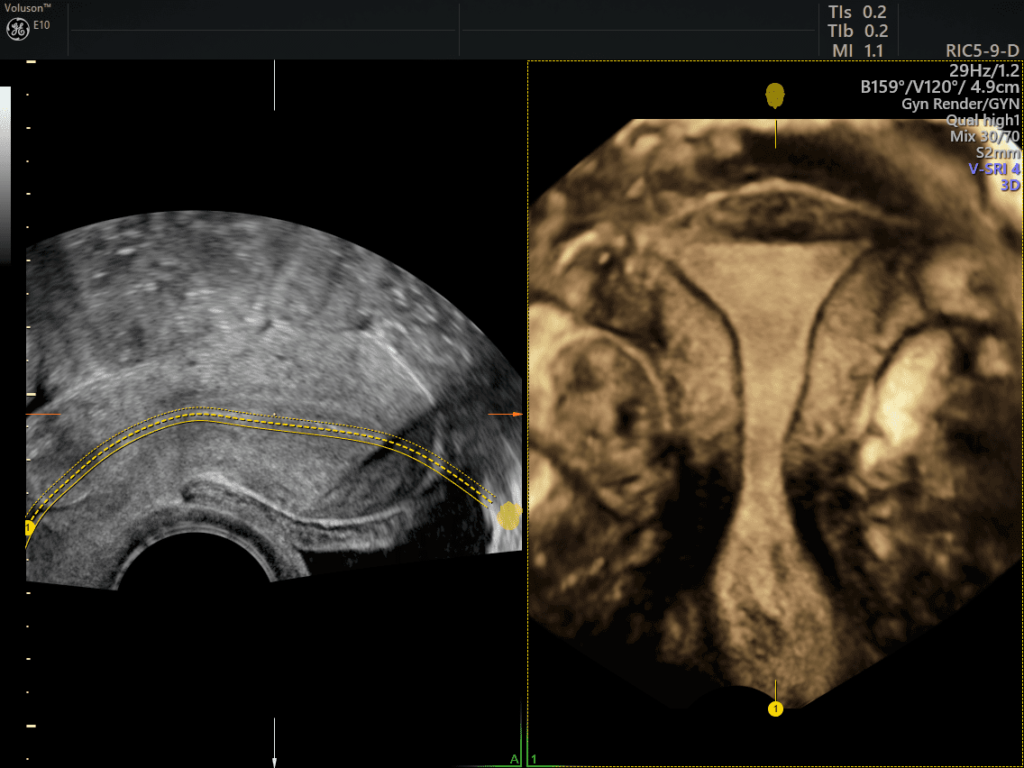

Uterine Trace: software per la ricostruzione automatica della cavità uterina.